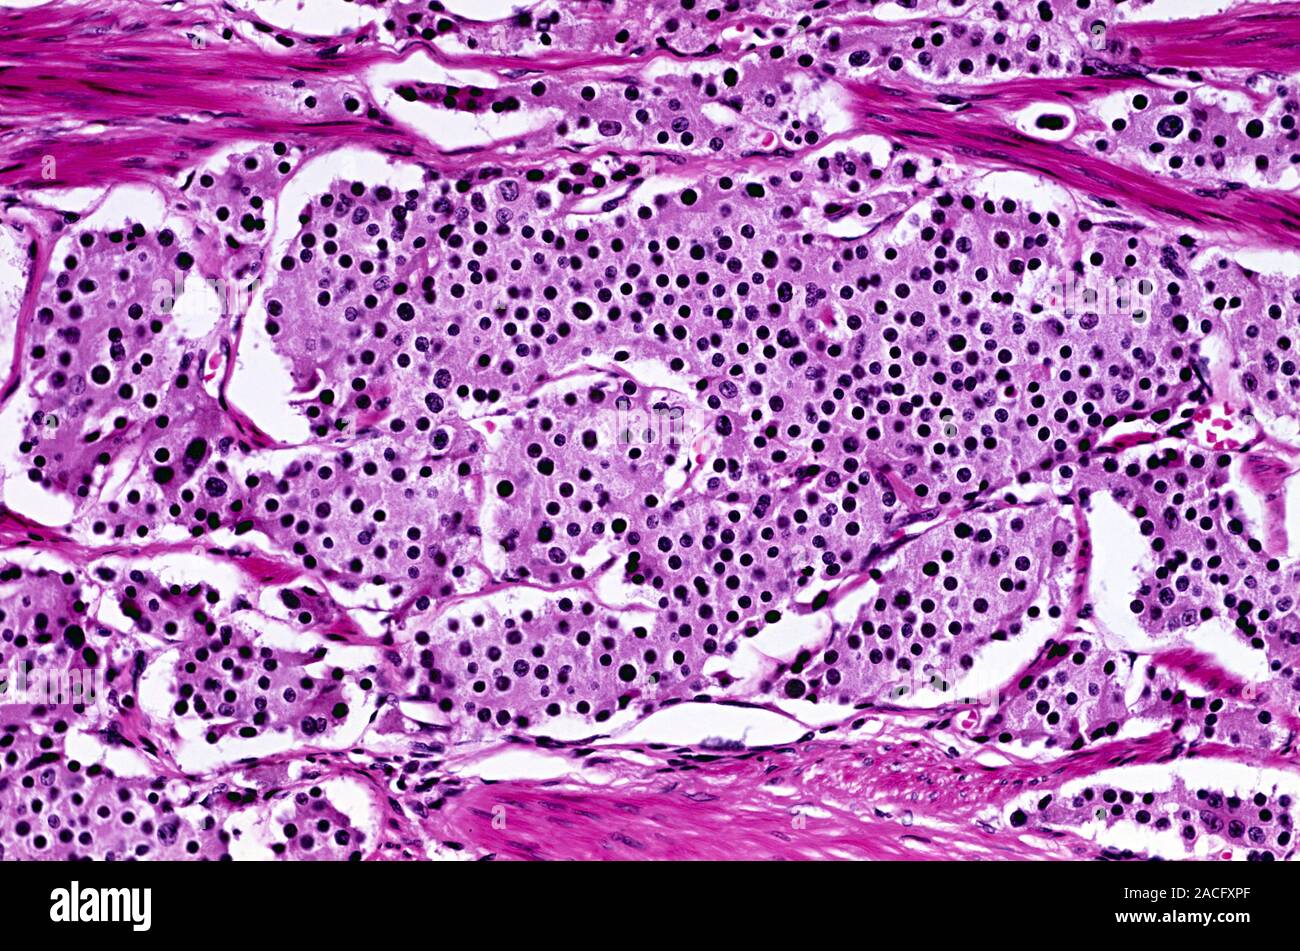

In pathology, an apudoma is an endocrine tumour that arises from an APUD cell from structures such as the ampulla of Vater. They were historically thought to be derived from neural crest cells, but this has since been shown to be untrue (see neuroendocrine tumor).The term dates back to at least 1975. Because the label "apudoma" is very general, it is preferred to use a more specific term when possible.